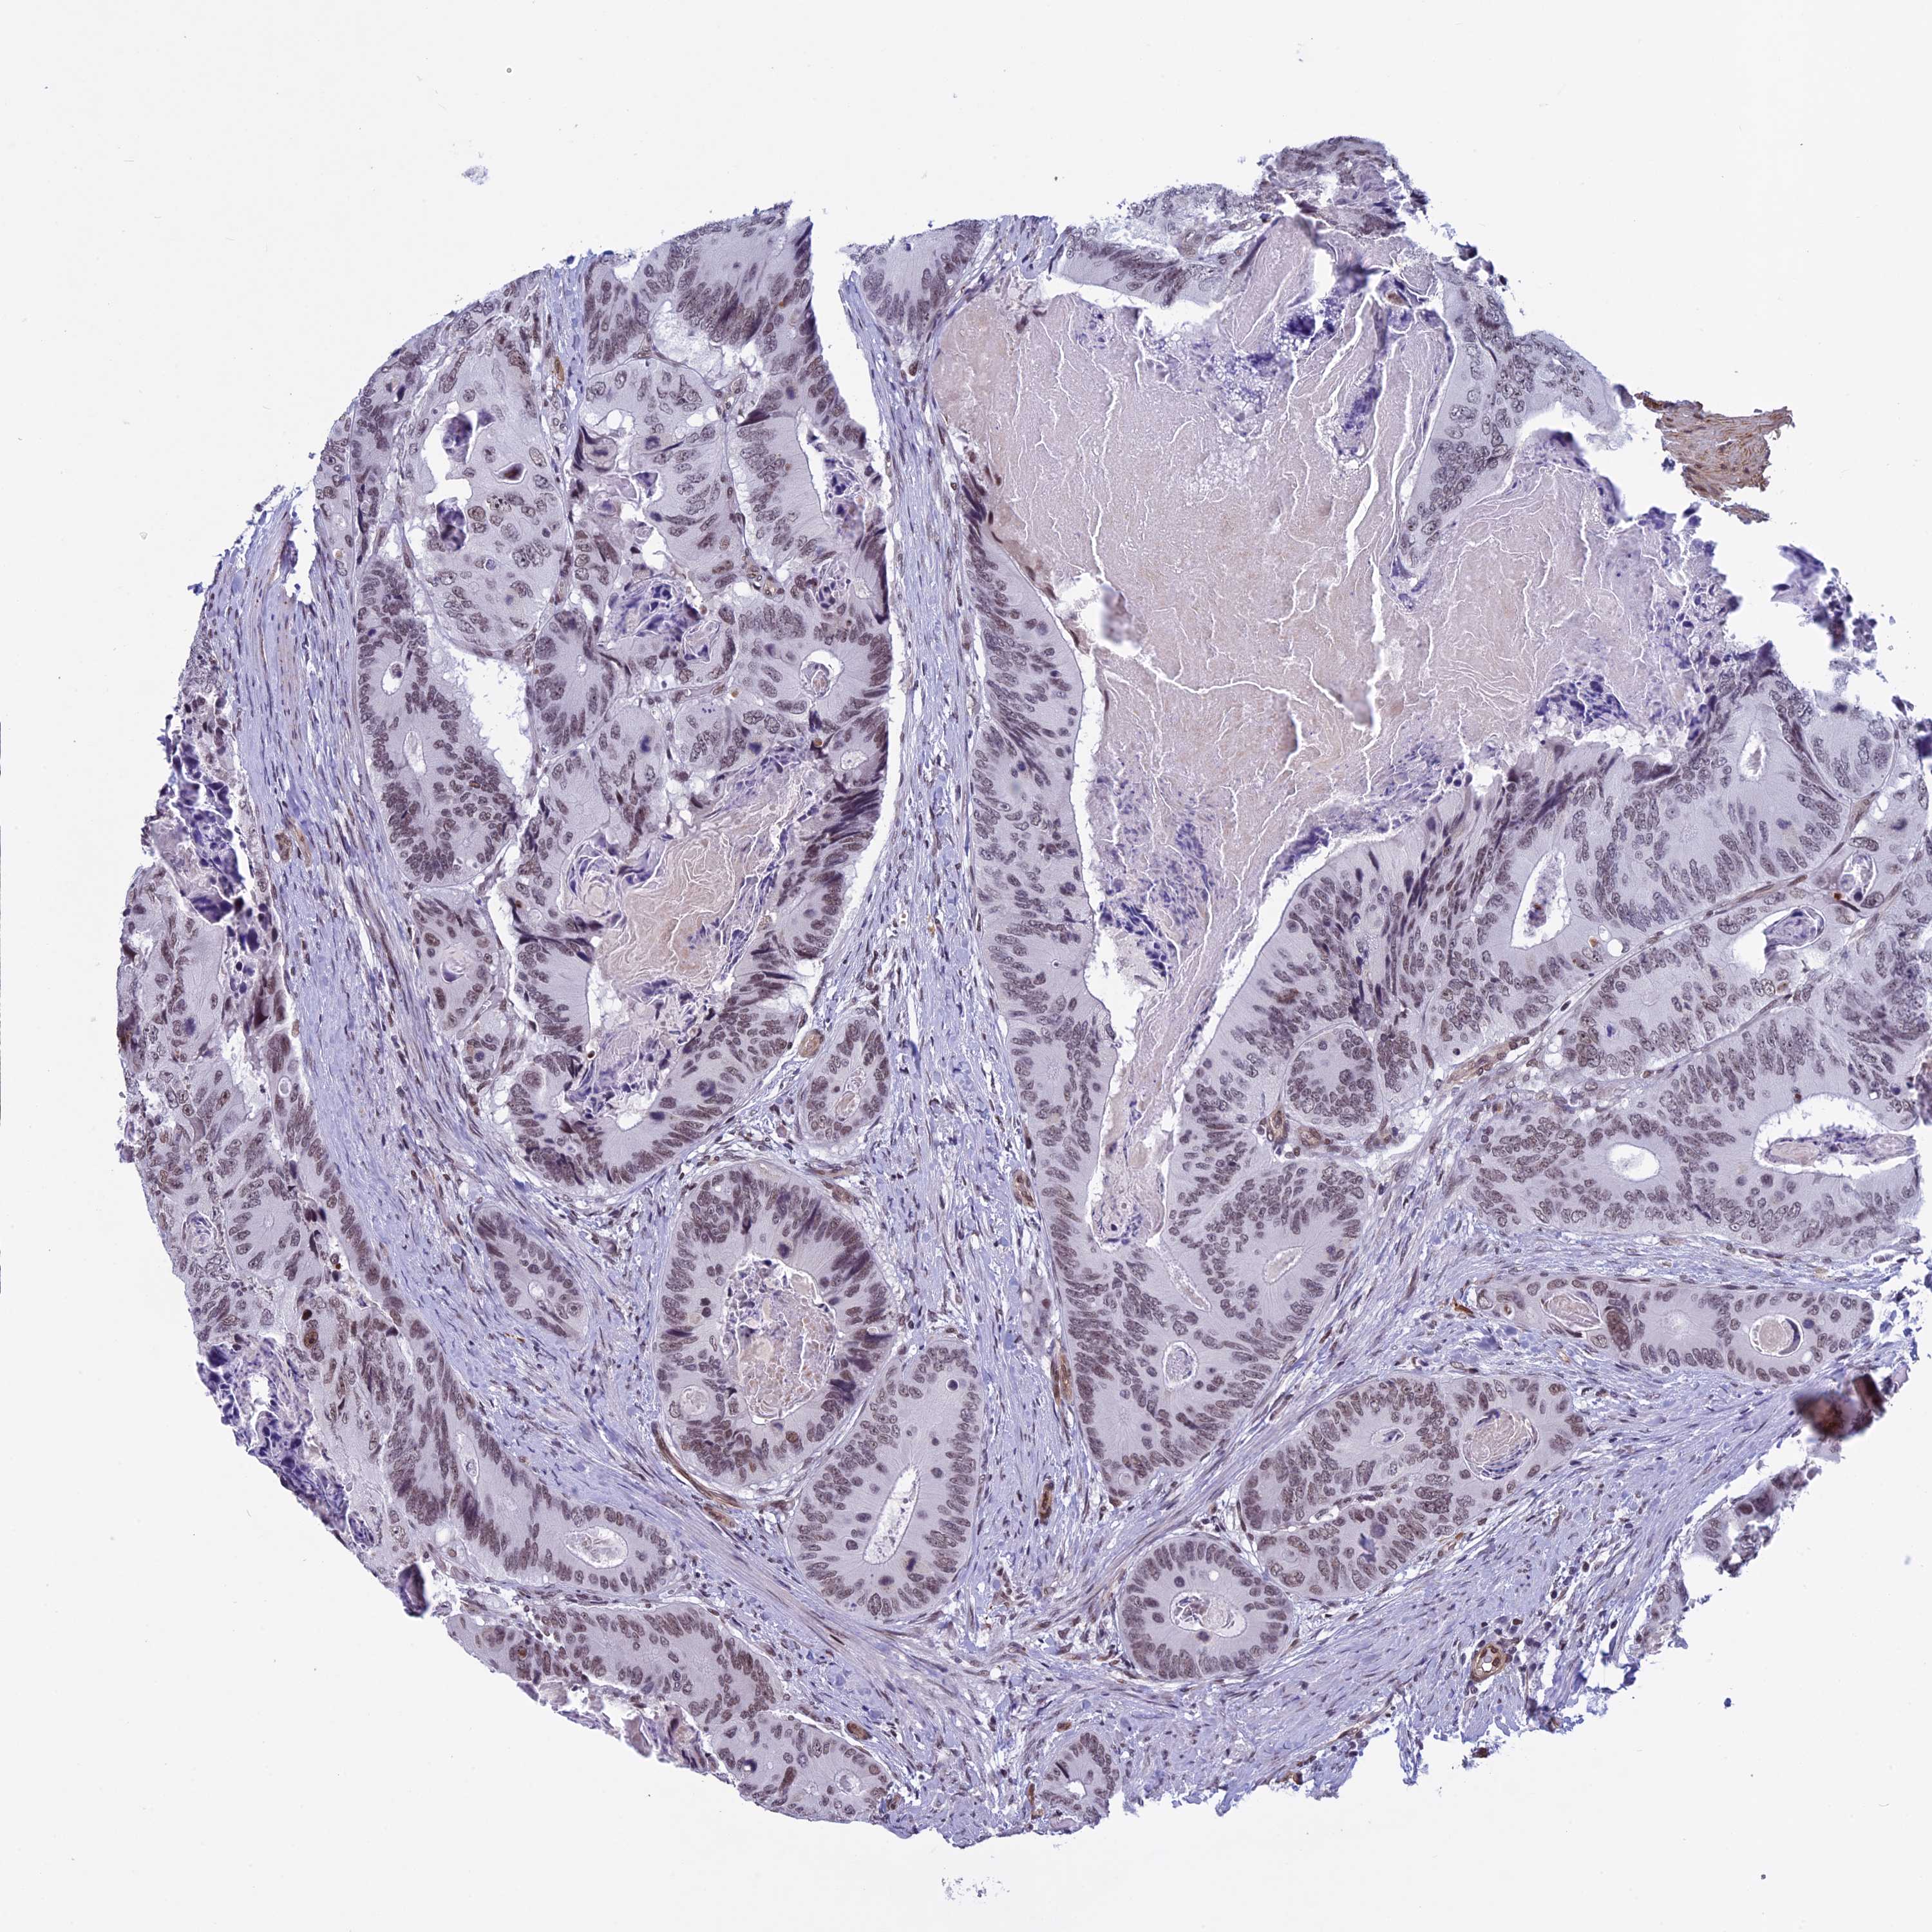

CANCER COLORECTAL CANCER Show tissue menu

Colorectal cancer

Colon adenocarcinoma